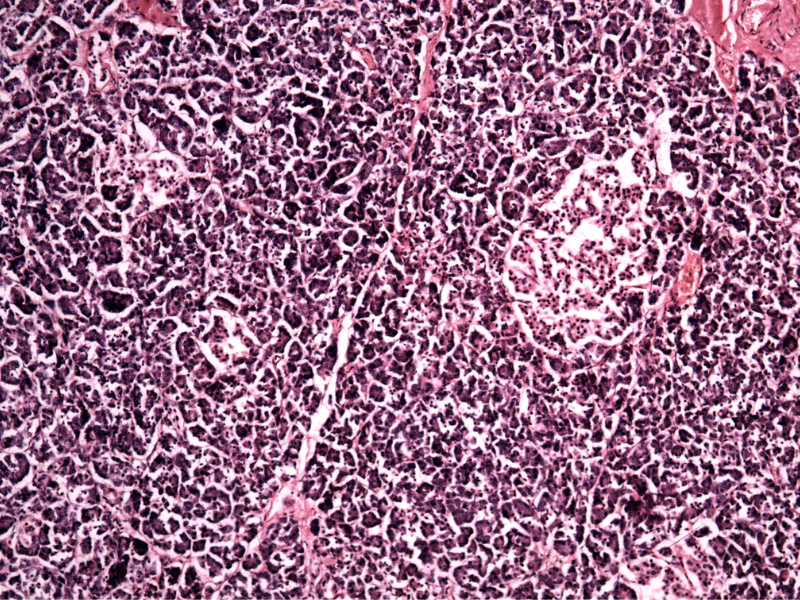

Endocrine and exocrine cells make up the pancreas. Exocrine cells produce enzymes secreted into the small intestine and aid in food digestion, whereas endocrine cells secrete hormones like insulin.

Exocrine cells called ductal cells line the tubes (ducts) that carry pancreatic enzymes. Previous research has revealed that stem cell offspring (ductal progenitor cells) can develop into beta cells that produce insulin.

They discovered that the EZH2 inhibitor-triptolide combination reactivated human ductal cells after 48 hours, restoring their progenitor potential and enabling their differentiation into beta-like cells. The cells produced insulin when exposed to a glucose solution.